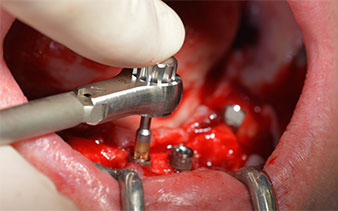

Prima di tutto, è stato individuato il forame mentoniero come limite della struttura anatomica. Successivamente, l'osso corticale della cresta è stato lisciato con un manipolo e una fresa larga a rosetta (Fig. 4).

A questo punto si possono già intuire i vantaggi che garantisce Implantmed. Il protocollo chirurgico è già predefinito e gli strumenti sono collocati in posizione fissa. Le posizioni individuali possono essere selezionate premendo la lettera "P" con il controllo a pedale o tramite il display. La velocità predefinita è di 35.000 giri/min nella posizione 1 e, in questo caso, i numeri sono visualizzati sul display illuminato (Fig. 5 e 6).

Il protocollo chirurgico per il sistema di implantologia utilizzato (SKY, Bredent medical) prevede una velocità di 1.200 giri/min per la perforazione pilota (Fig. 7 - 9).